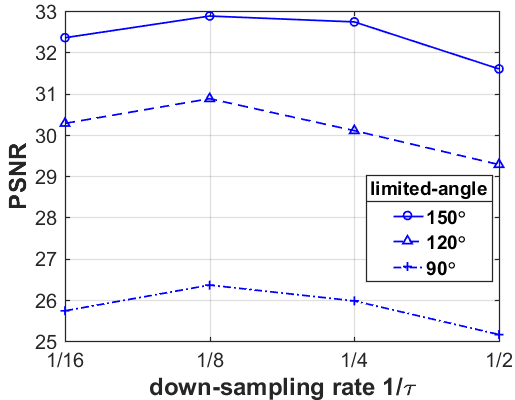

What is more, as shown in Table III, IV and V, the smaller the down-sampling rate, the better the reconstruction result. Since the quality of the image prior decreases as the resolution decreases for the limited-angle reconstruction problems, there is a trade-off between the resolution and the quality. Thus, we track the relationship between the resolution of the low-resolution image priors and the performance of our LRIP-net. As shown in Fig. 9, the best reconstruction results are obtained using the low-resolution image prior with down-sampling rate . Although the smaller the condition number of the system matrix, the better the numerical stability of the solution, it does not mean that the better the performance of our LRIP-net.